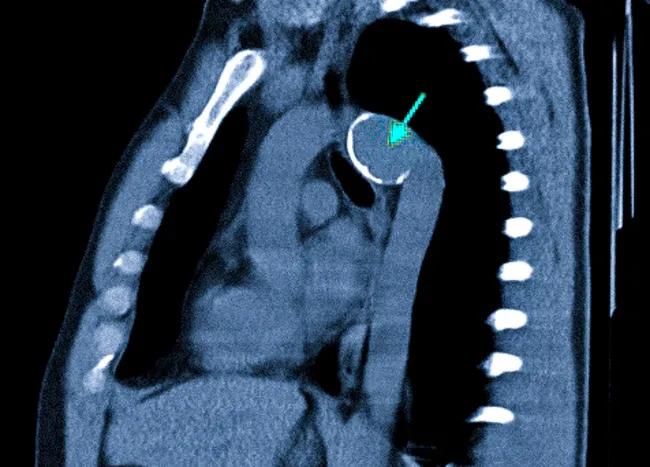

Реконструкция левого желудочка (РЛЖ) — это операция, в ходе которой хирург изменяет геометрию левого желудочка, чтобы улучшить его способность перекачивать кровь. После крупного инфаркта миокарда часть сердечной мышцы погибает и замещается рубцовой тканью. Этот рубец не сокращается и со временем под давлением крови может растягиваться, образуя аневризму — мешковидное выпячивание стенки сердца. В результате левый желудочек увеличивается в объеме, теряет свою эллиптическую форму и работает неэффективно, что приводит к развитию или прогрессированию сердечной недостаточности.

| Магнитно-резонансная томография (МРТ) сердца с контрастированием | Позволяет с высокой точностью определить границы между рубцовой и живой тканью миокарда. Это ключевая информация для хирурга, чтобы спланировать объем вмешательства. |

- Выполнение РЛЖ. Хирург вскрывает полость левого желудочка, находит зону рубца (аневризмы) и либо иссекает ее, либо отграничивает специальной заплатой (чаще всего используется методика Дора). Края здоровой мышечной ткани сшиваются, восстанавливая эллипсоидную форму и уменьшая объем желудочка.